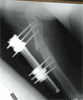

Post Op

Excision of malunion,gentamicin beads insertiion with acute shortening and distal corticotomy to restore length with Ilizarov frame applied

Progress

Healing of malunion in good alignment and length restoration